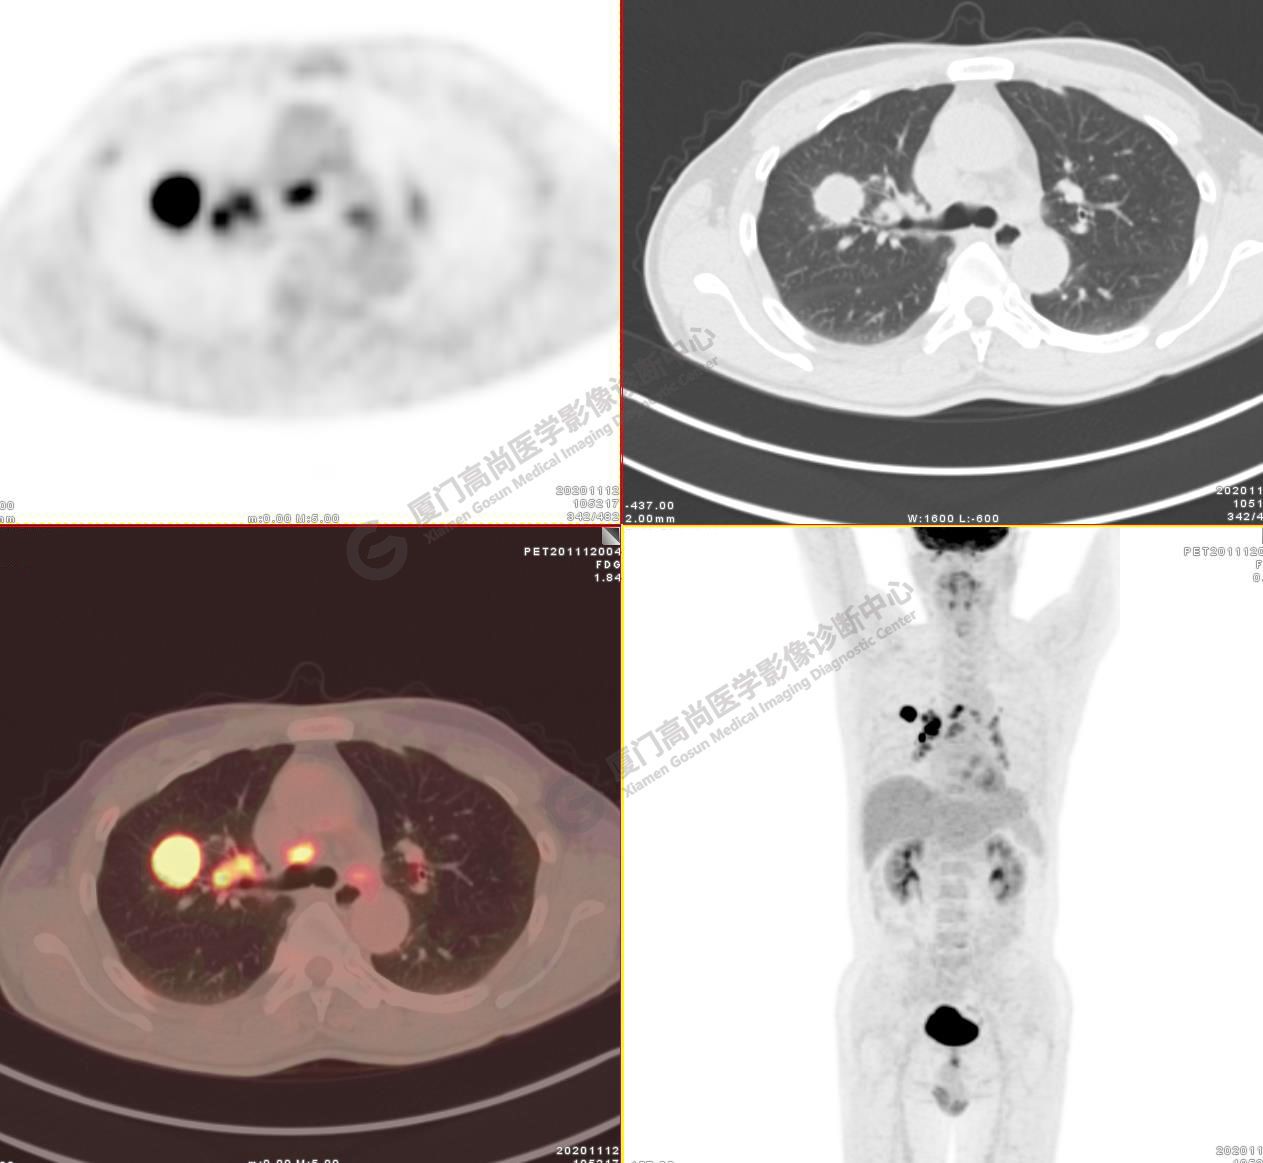

病例2:某男士,53歲,2020年4月單位體檢,CT,發(fā)現(xiàn)右肺上葉結(jié)節(jié),性質(zhì)待定

右肺上葉前段見一類圓形實性結(jié)節(jié),大小約2.8x2.6cm,邊緣見分葉、毛刺,前段支氣管阻塞。FDG攝取增高,SUVmax16.5,右肺門及縱隔見多發(fā)腫大淋巴結(jié), FDG攝取增高,SUVmax13.1,遠處未見FDG高攝取病灶 。

影像診斷:右肺上葉周圍型肺癌并右肺門及縱隔淋巴結(jié)轉(zhuǎn)移。

( TNM分期,T1cN2M0 ⅢA期)

病理診斷 :低分化腺癌